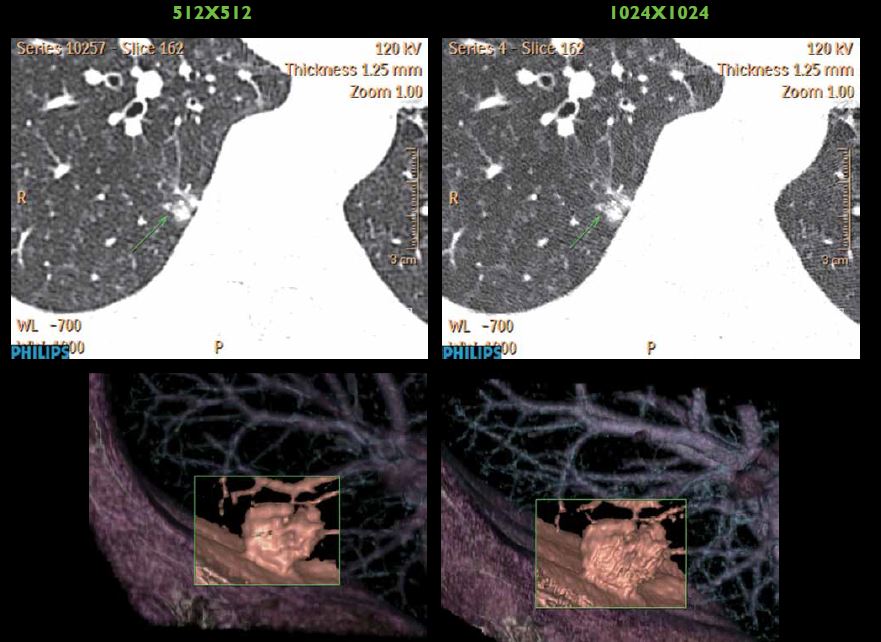

纤毫毕现

显微成像——动态四焦点及纳米探测器实现4800采样/0.27秒最高采样率,丰富信息成就1024x1024超高分辨成像技术,4倍信息量提升令微小病灶诊断不再困惑。同时高效的祛金属伪影O-Mar功能防止漏诊情况。

1024x1024高清成像对于肺结节显示加倍的清晰